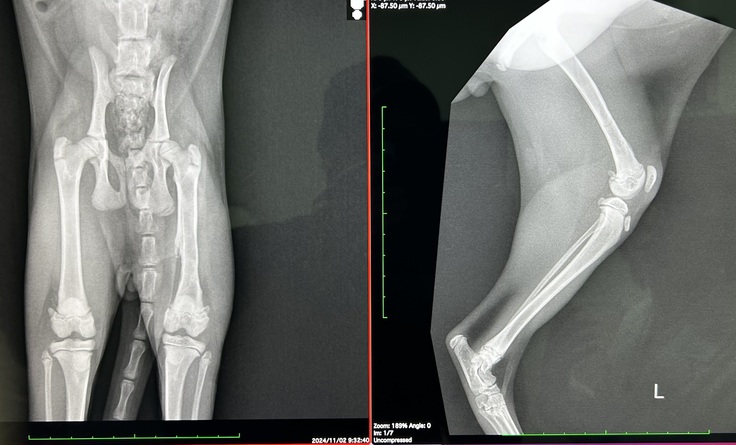

本日は9/26の抜糸以来の手術病院での診察です。

約1ヶ月のリハビリ結果とカクカク歩きの原因や対処について相談する予定で行きました。

本日の診察では、良くなっている部分と懸念が残る部分があり、それぞれ先生からご意見をいただきました。

【良くなっている部分】

◯ 左脚が使える状態になっている。

→ 骨折の影響で左脚を引きずっていましたが、リハビリを続けた結果、現在では左脚を使えるようになりました。

◯ 神経反応は確認

→ 脚気反応や脚先の神経反応が確認され、神経麻痺などの懸念はなくなりました。

【懸念が残る部分】

◯ カクカク歩行

→骨折で脚を使えない影響で、筋肉が硬くなり曲げ伸ばししきれない。

→大腿神経の影響で、体重をかけられない可能性があること。

先生は「これをすれば確実に良くなる」という明確な方法は現段階では言い切れないと正直に話してくださいました。ただ、ごろうは生後4ヶ月の成長期の子なので、改善の可能性を信じてできることを試していくことが大切だとアドバイスを受けました。これが将来のごろうにとって良い結果につながるかもしれません。